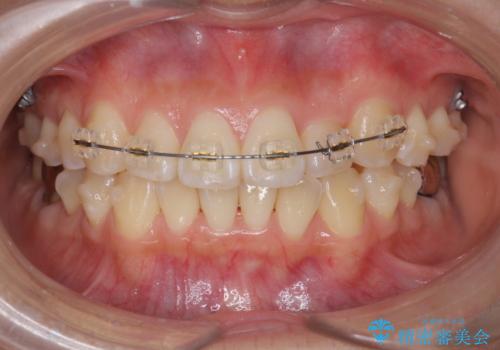

マウスピース矯正システムインビザラインで歯の後方移動、咬合関係の修正を行ったのち、引っ込んでいる左上2をワイヤーを用いて短時間で引き出す治療計画としました。

部分ワイヤー矯正を行なったことで約3ヶ月という短期間で前歯を綺麗に並べることができました。